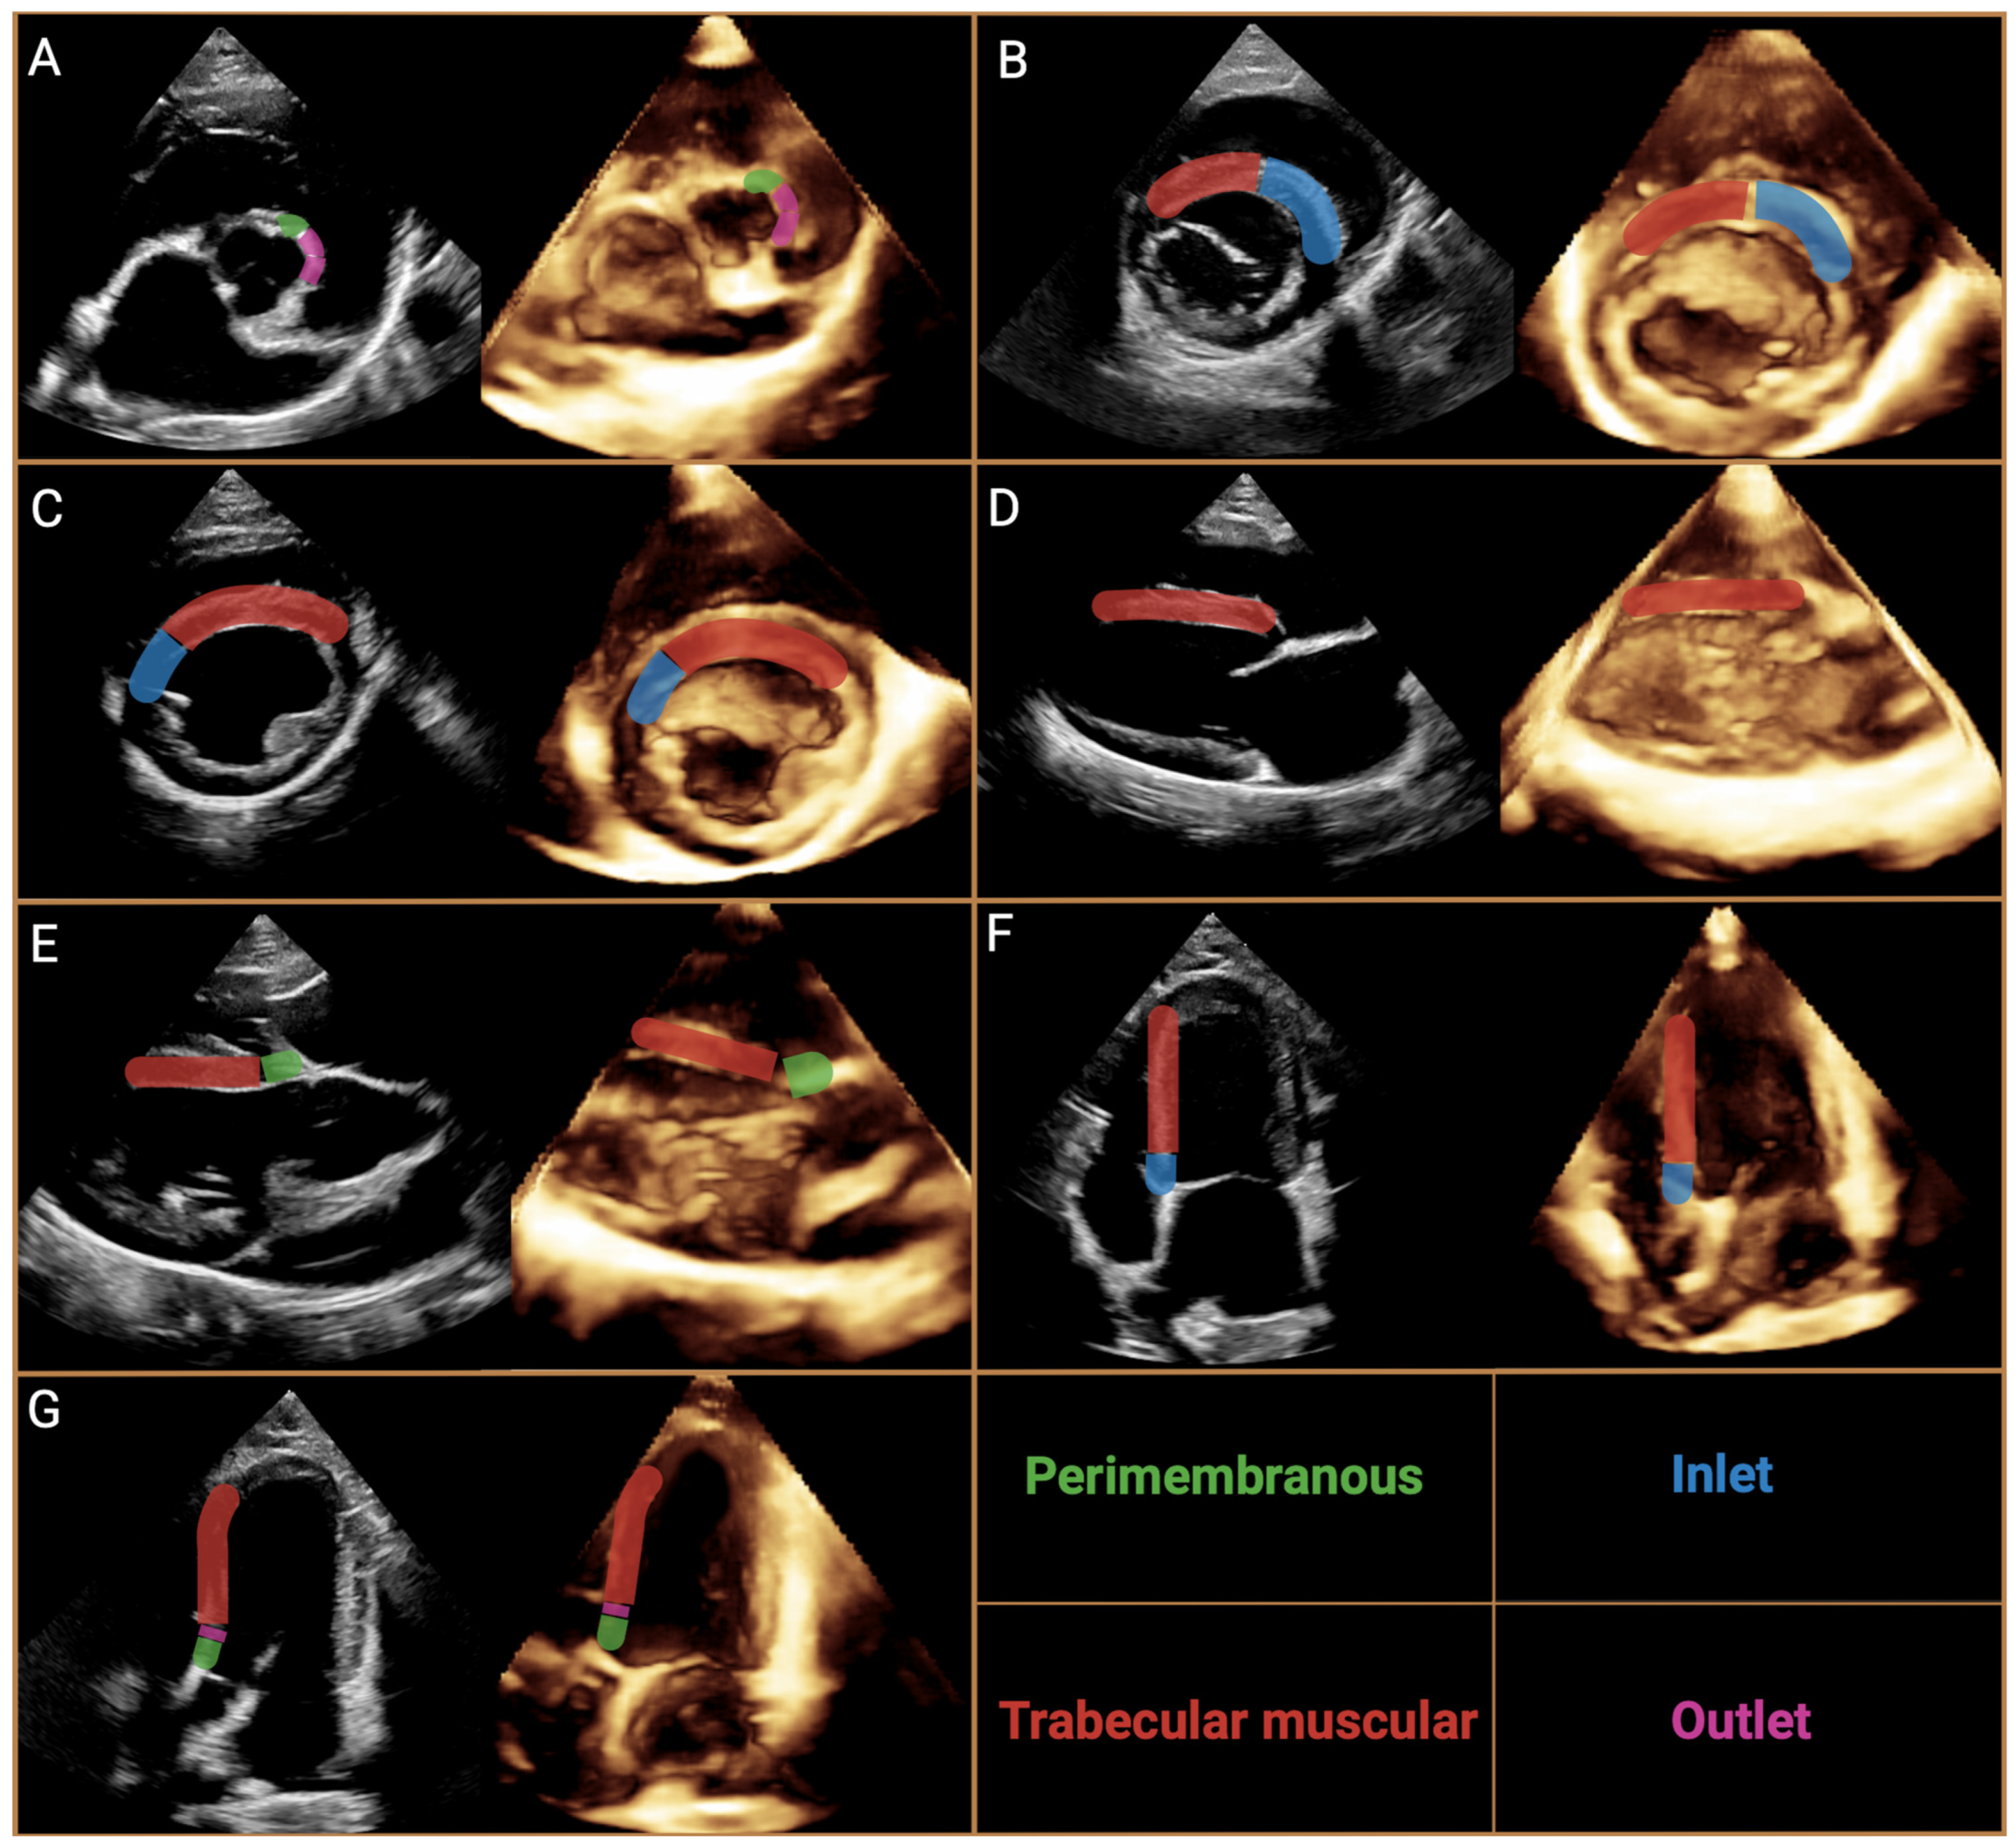

4.2. Echocardiography, Radiography, ECG Findings